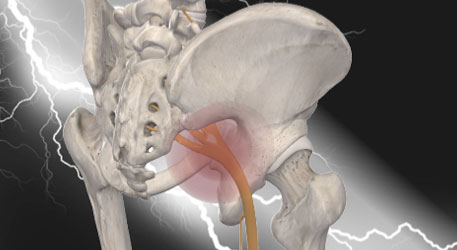

坐骨神経とは、腰からお尻、太もも、ふくらはぎを通って足の親指近くまで繋がっている、人体で最も太い神経です。

「坐骨神経痛」とは、その坐骨神経が何らかの原因で障害されて起きる足の痛みやしびれの『症状』のことをいうため、『病名』ではありません。

特に先ほど挙げた「腰椎椎間板ヘルニア」と「梨状筋症候群」は併発しているケースが非常に多く、どちらか一方を見逃してしまうことで、症状の改善が遅れてしまうリスクがあるのです。

腰から足にかけて、しびれる範囲に沿って、かつ神経が通っている深部まで届くように電気をかけ、神経の正常化を行います。

表面的な「ピリピリ感」や「電気の痛み」はほとんどなく、代わりに、しっかりと深い部分にも電気が入って、効いている感覚があるはずです。